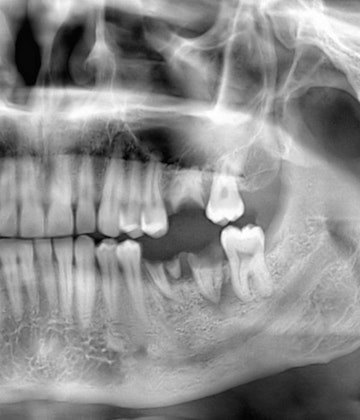

A Closer Look At Dental Implants

Whether you are missing one tooth or several teeth, dental implants can secure your stunning new dental restoration.